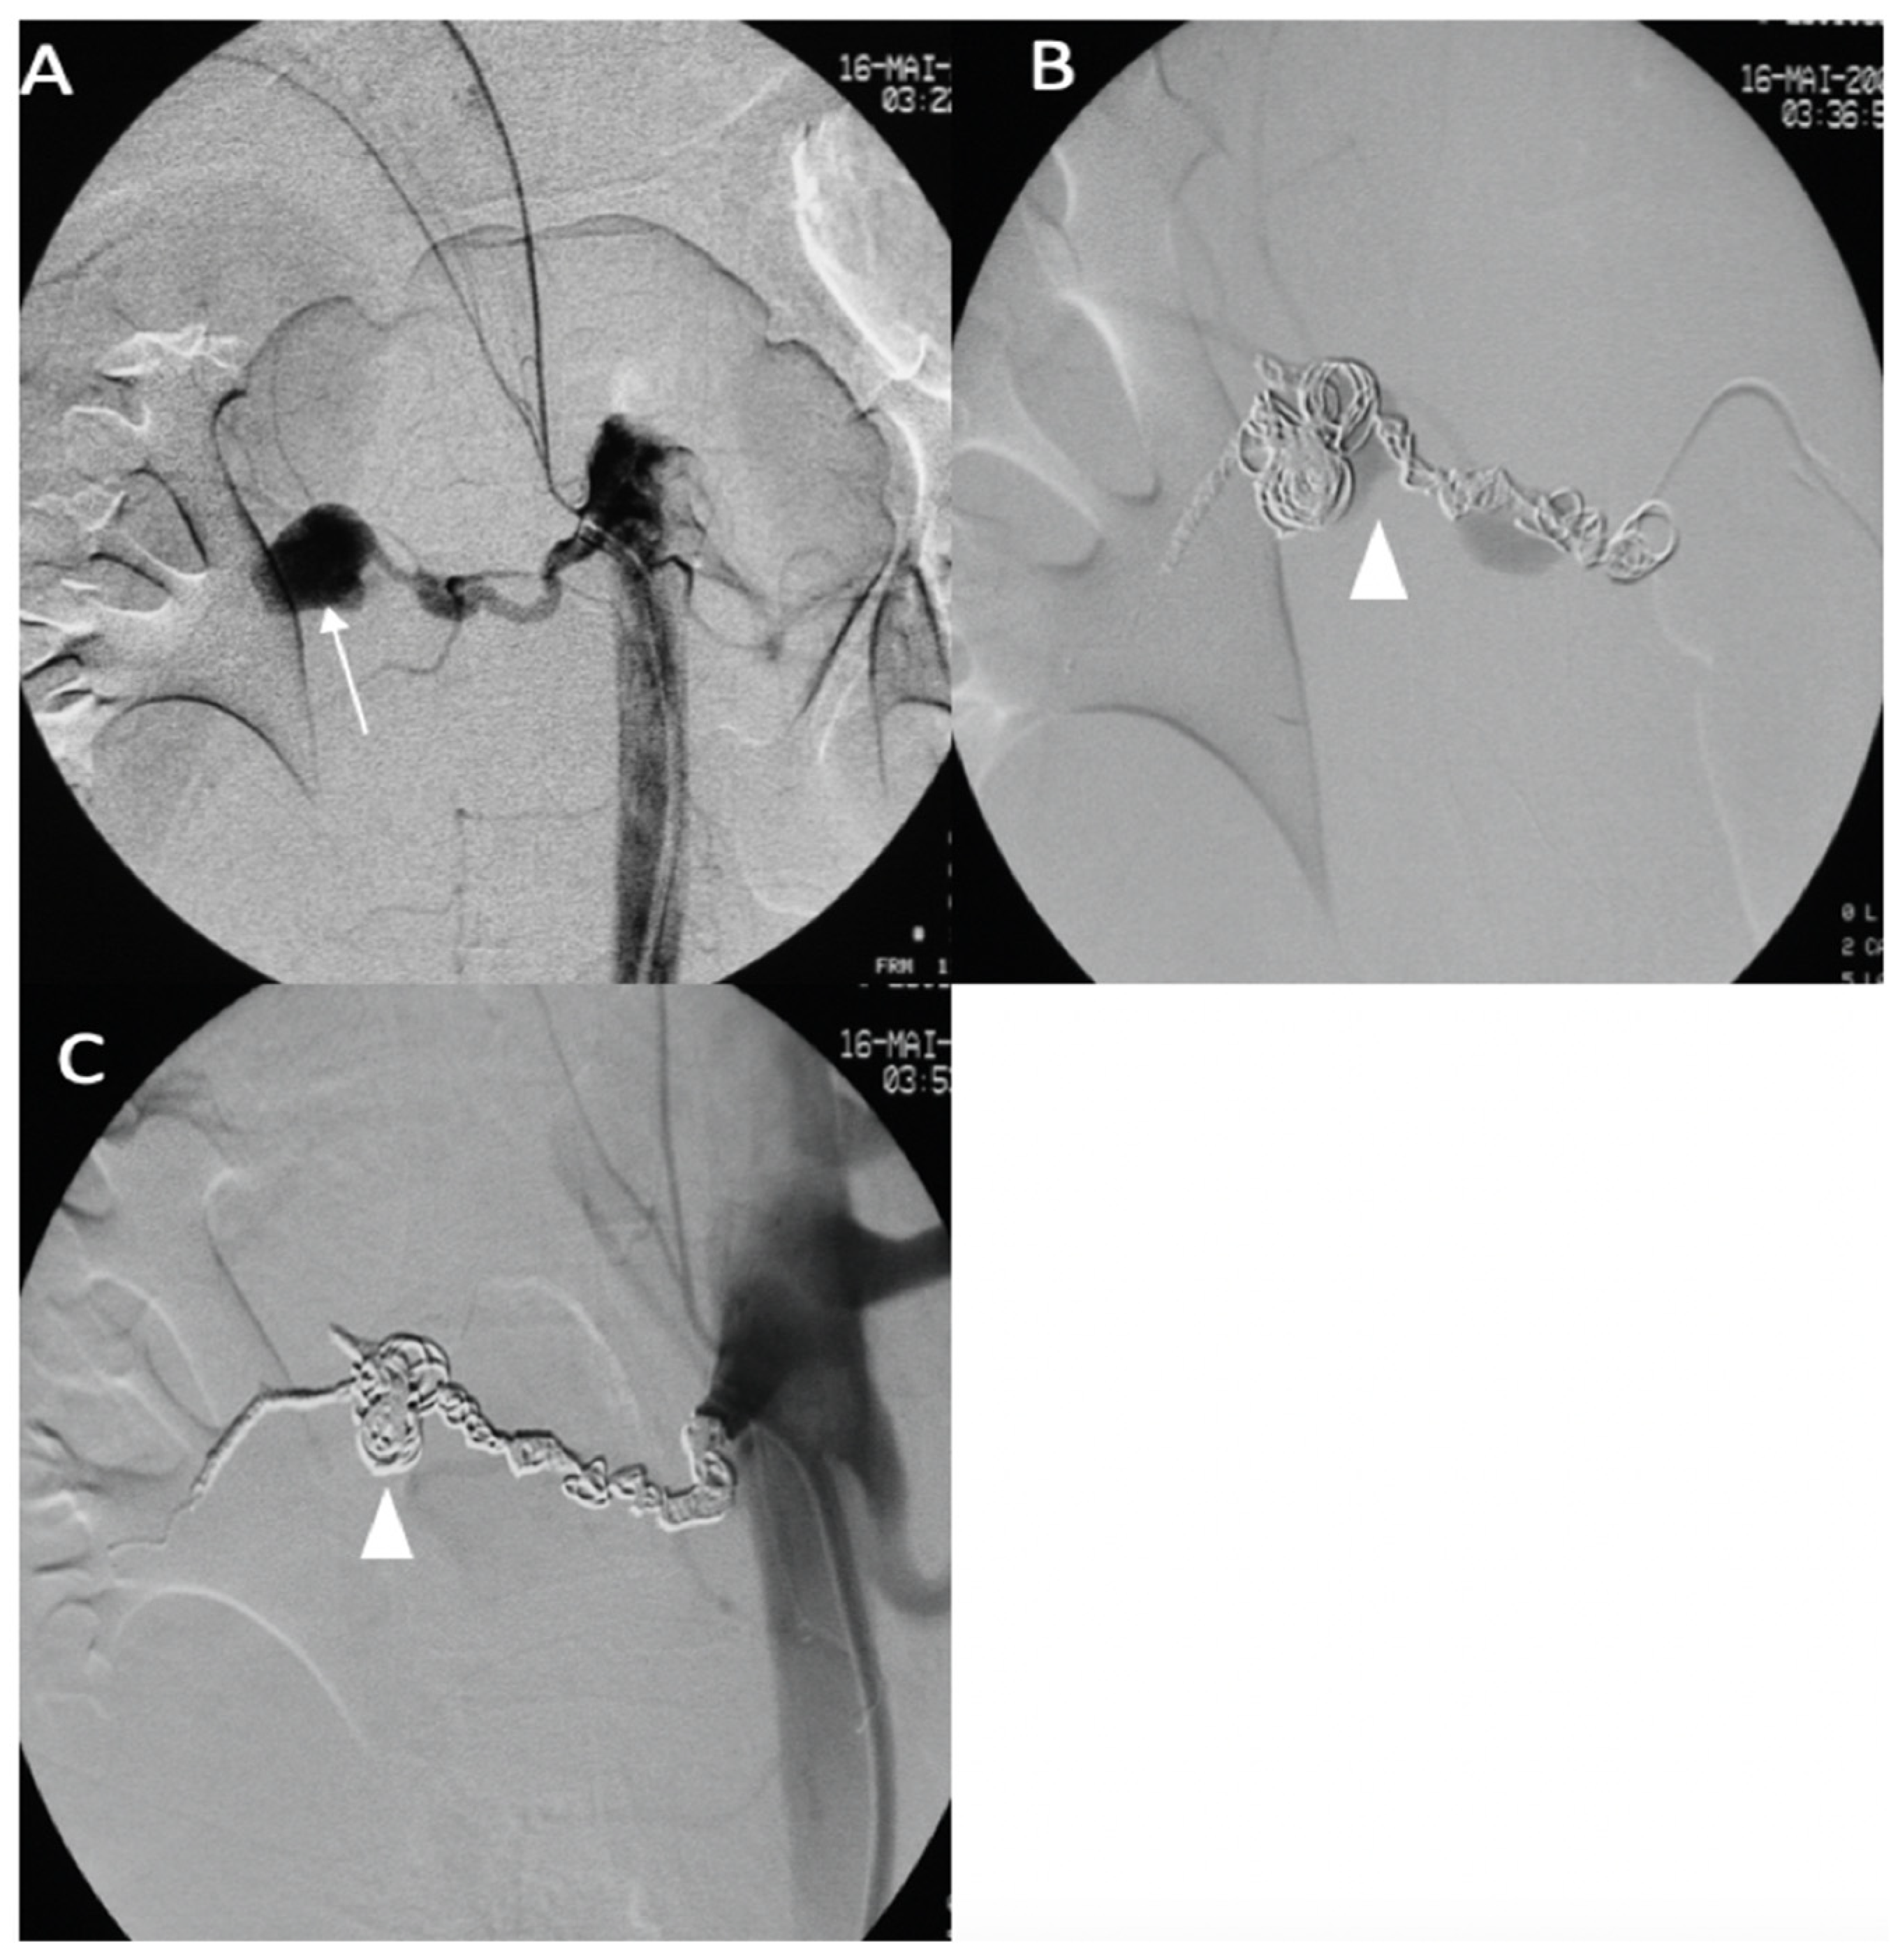

A 25-year-old female patient with pre-symptomatic vEDS was referred to our hospital for acute left-sided hemiplegia and transient right arm hemiparesis. Magnetic resonance imaging (MRI) cerebral and CT angiography of the supra-aortic trunk demonstrated a sub-occlusion of the right middle cerebral artery, along with a severe hypoperfusion of the right internal carotid artery related to dissection and an intramural hematoma of the left internal carotid artery. Her medical status was a contraindication to thrombolysis, and the stroke team decided to refer her to the interventional neuroradiologist. Under general anesthesia, an 8 F introducer was inserted via the right femoral artery. Right common carotid artery access was obtained using a 7 F NEURON MAX catheter (Penumbra-Alameda, CA, USA) and a TERUMO 0.035 guidewire. DSA revealed an occlusion of the dissected right internal carotid artery and an occlusion of the proximal portion of the middle cerebral artery (M1) (Figure 6A). Aspiration through a dedicated catheter (Sofia 6 F TERUMO) of the M1 thrombus was unsuccessful (Figure 6B,C). The thrombus was then successfully removed using a Headway microcatheter (0.027), Terumo microwire (0.016), and stent retriever (Solitaire 4 × 20), with good outcome (Figure 6D). The right internal carotid artery dissection was treated through the deployment of a 7 × 50 mm carotid wall stent in the extracranial portion of the right internal carotid artery (Figure 6E,F).

Figure 6.

(A) Digitally subtracted image from the right common carotid angiogram showing occlusion over the dissection of the right internal carotid artery (star); (B,C) crossing the dissection by a Sofia 6 F aspiration catheter (arrows) and the occlusion of the proximal portion (M1) (arrowhead); (D) anterior view after mechanical thrombectomy; (E,F) anterior and lateral views after the deployment of the carotid wall stent.

No complications occurred during the procedure or during the postprocedural hospital stay. A few months later, she developed a dissecting aneurysm in the right internal carotid artery after the stent, which was monitored by Doppler ultrasound. After 3 years of follow-up, she did not have any other arterial event under celiprolol therapy and presented with persistent left hemiparesis.